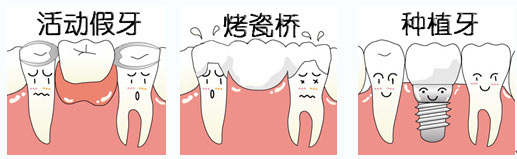

1、舒适:种植牙不会让患者有恶心干呕等异物感。

2、牢固:因为种植牙的人工牙根是植入在牙槽骨上,就像真牙扎根于口腔一样。

3、不磨牙:种植牙有自己独立的牙根,所以不需要磨损临近的牙齿。

4、无痛:种植牙的手术是一个小型的外科手术,手术过程完全无痛,术后即可进食。

5、美观:种植牙的形态和颜色都是根据患者量身定制,外观上所以更加美观、自然。